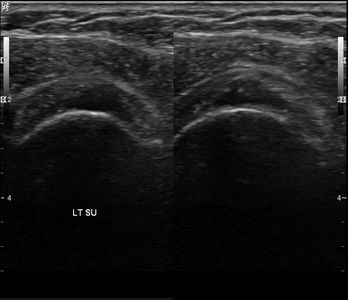

50세 남성

회전근개파열

Before

2019.11.04

After

2020.01.20

62세 여성